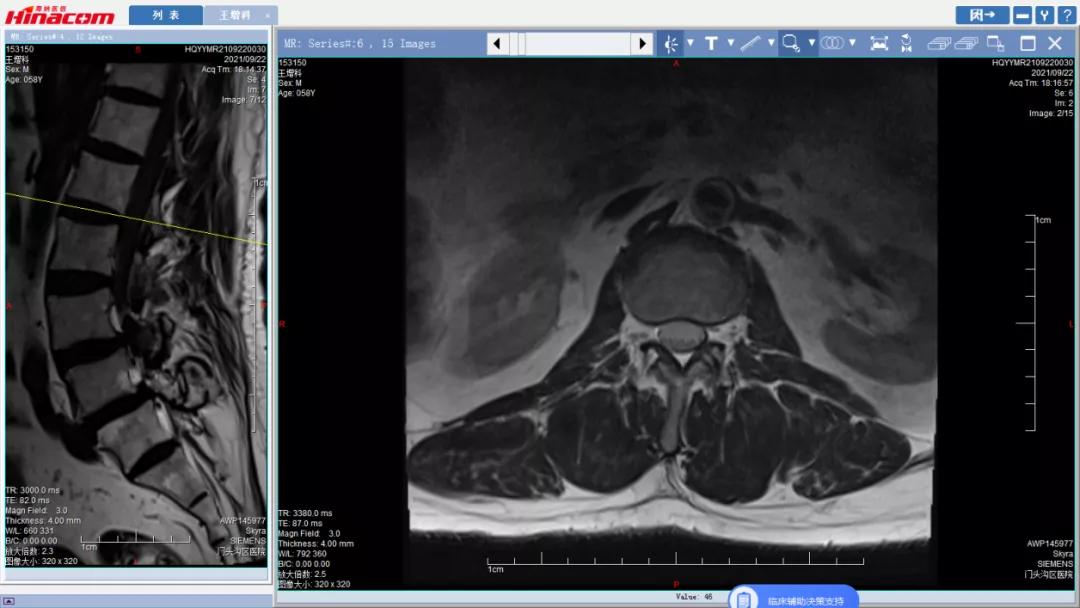

腰椎管矢状面--术前MRI

腰34椎管水平面--术前MRI